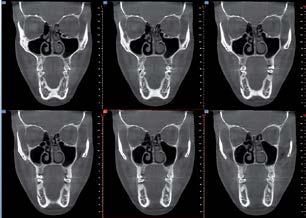

Nell’ambito della radiologia 3D ortopedica, il centro diagnostico utilizza il nuovissimo macchinario NewTom 5G XL, in grado di individuare con la massima precisione la presenza di fratture o lussazioni delle articolazioni, controllare la corretta guarigione di una frattura, valutare una lesione o una ferita causata da infezione, artrite o crescita anormale dell’osso.

Il tutto mediante una semplice e veloce scansione, grazie alla quale si otterranno diverse immagini in 3D ad altissima risoluzione e, per ottenere immagini ancora più nitide mediante un bassissimo dosaggio di radiazioni, gli esperti si avvalgono dell’innovazione racchiusa nella tecnologia Cone Beam.

Se con la radiologia tradizionale era necessario eseguire scansioni multiple, la novità introdotta dal macchinario NewTom 5G XL risiede nella capacità di fornire immagini ad alta risoluzione in un’unica scansione, mostrando nitidamente i dettagli delle articolazioni degli arti superiori e inferiori. Inoltre, a differenza della tecnologia 2D, la radiologia 3D ortopedica permette di individuare immediatamente alcune patologie come quella del metatarso, la quale richiede un allineamento visivo dedicato o una diagnosi delle micro fratture ossee.